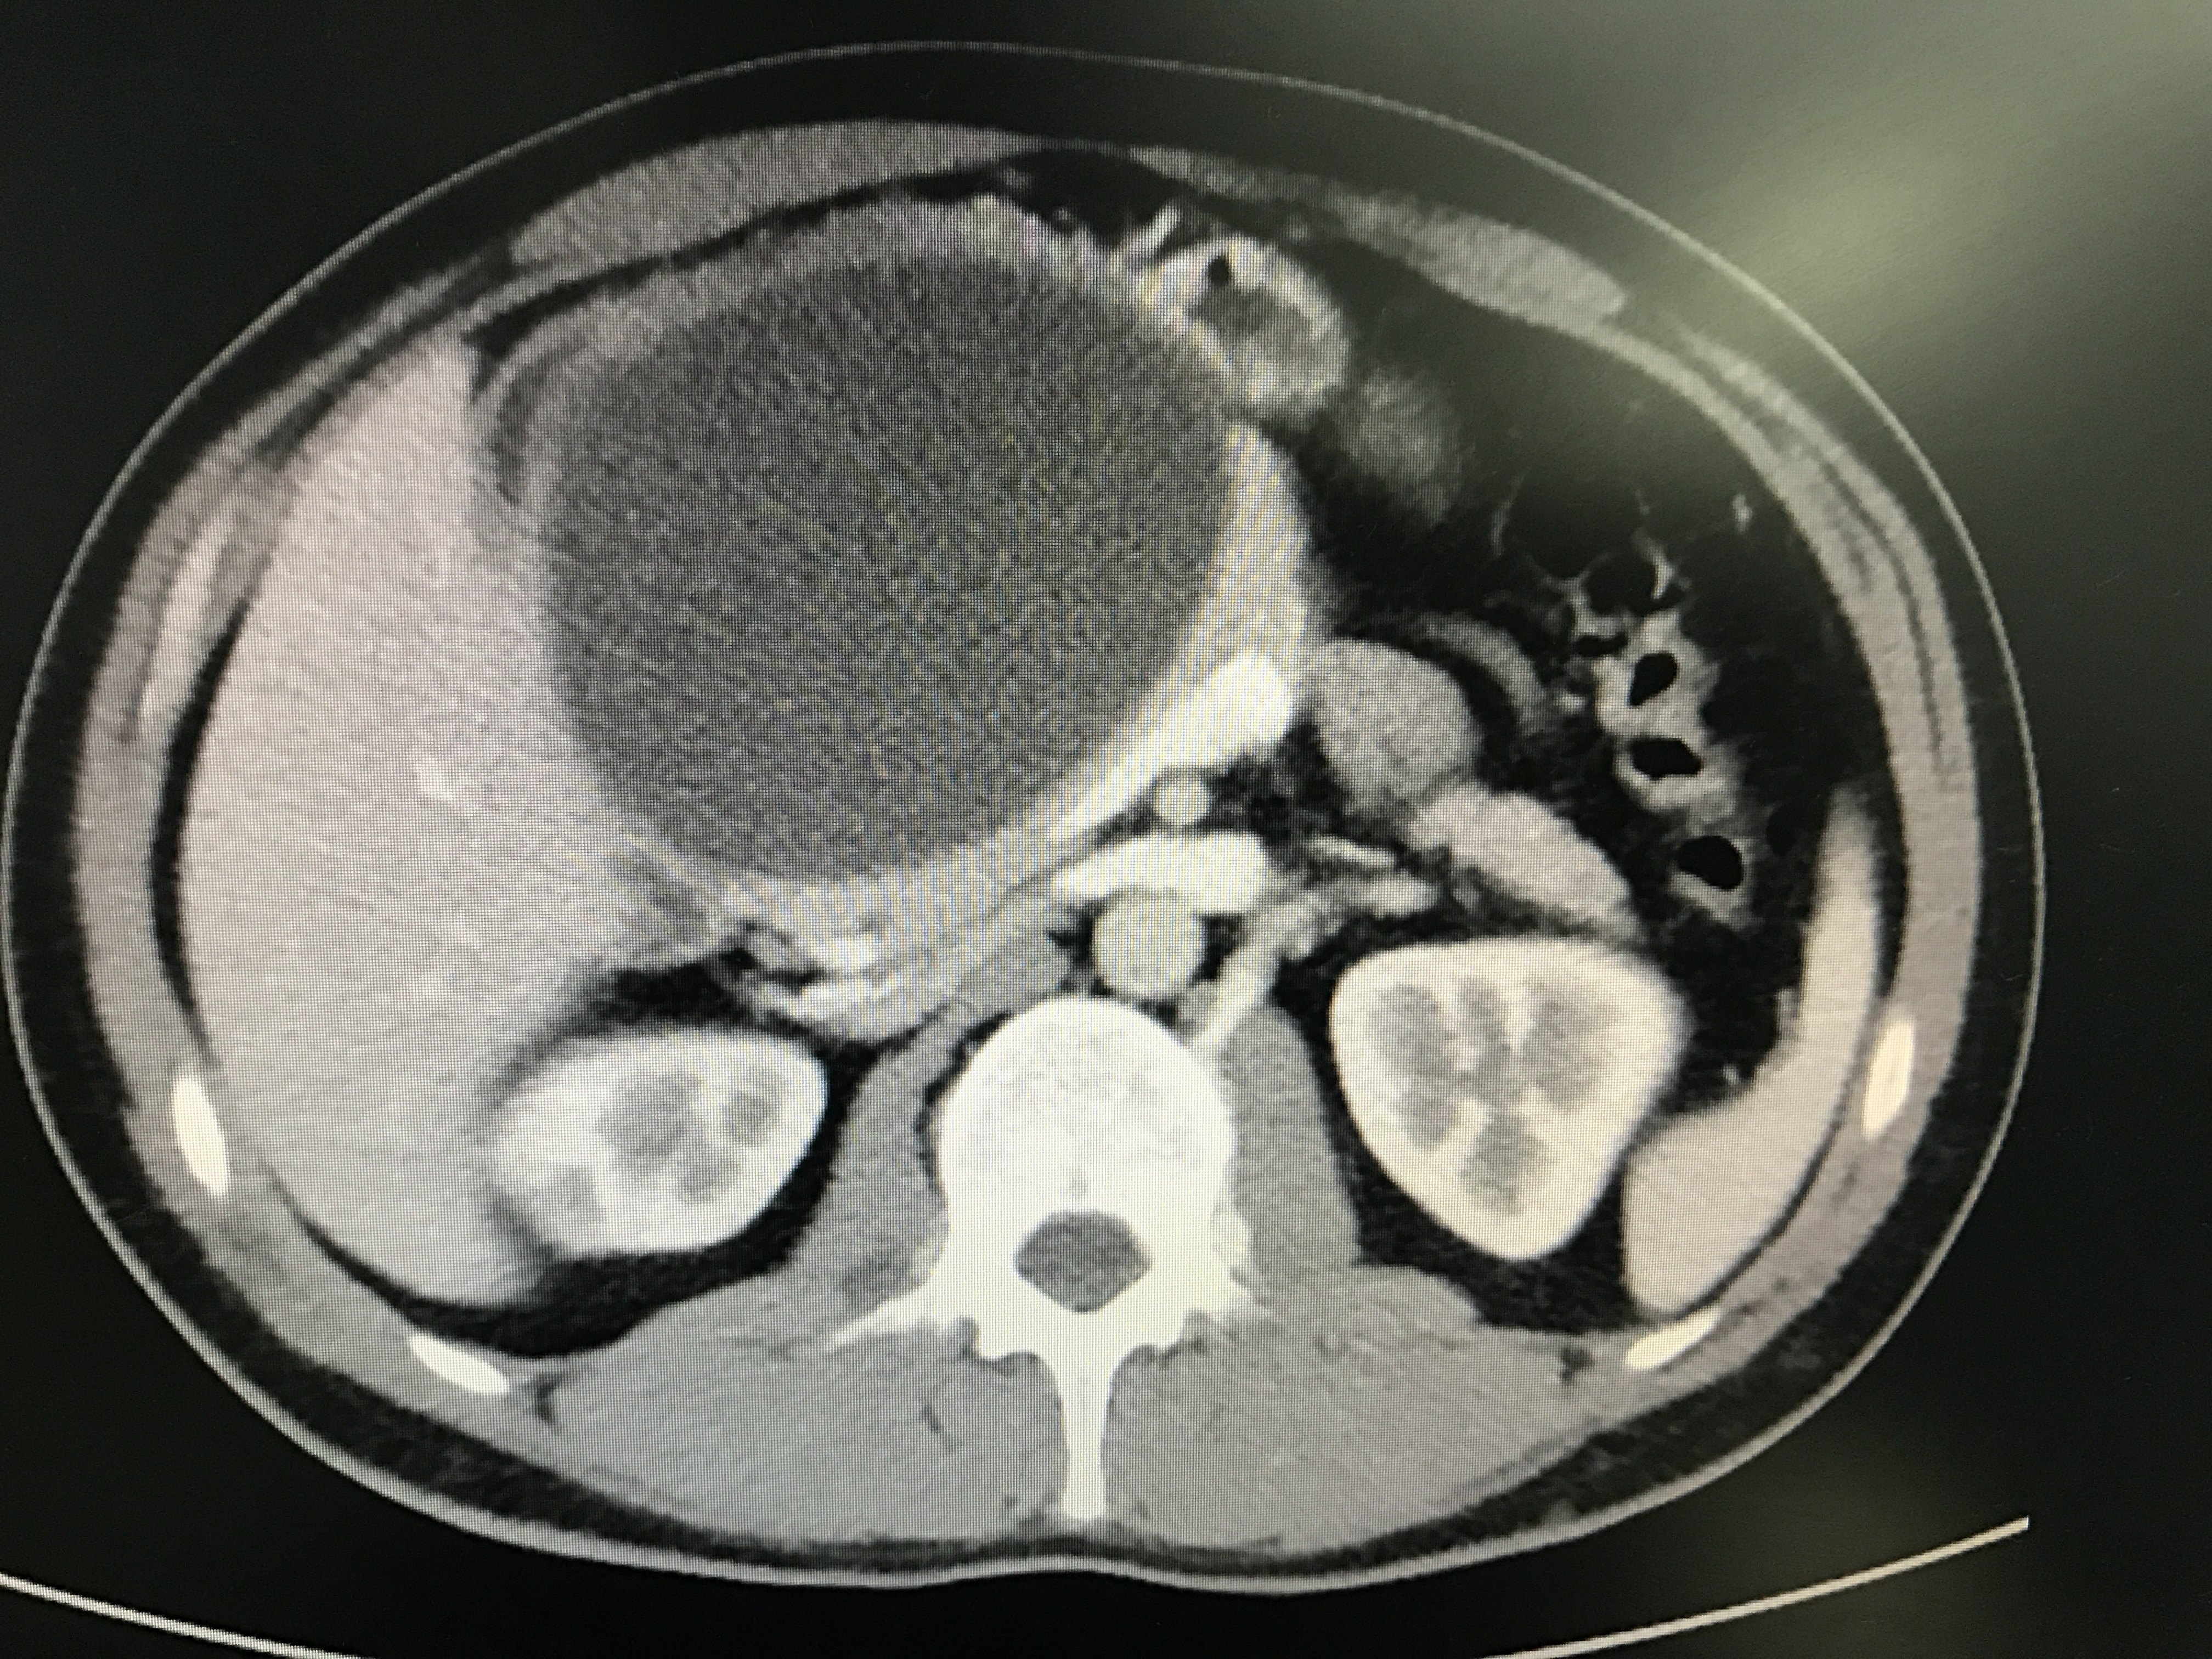

4032x3024 - 2760KB - JPEG

胰腺囊肿,现在5.5厘米大胰腺囊肿,去年3厘米,现在长到5.5厘米,最近经常可以微创吗,有没用药物可以治疗

部分胰腺囊性病灶需要手术,我院可以进行微创治疗。没有症状的话囊肿小于5cm的话可以不采取手术治疗,反之